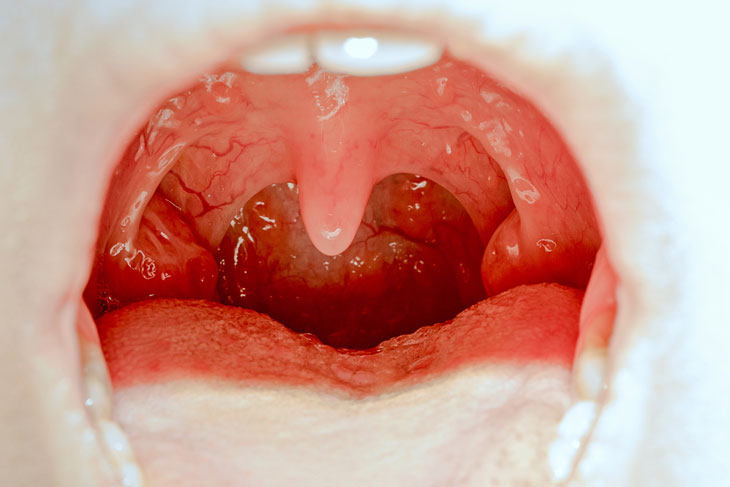

Viêm amidan

Với vai trò quan trọng trong việc giúp cơ thể sản sinh ra kháng thể chống lại sự xâm nhập của virus, vi khuẩn gây bệnh nên amidan có thể bị viêm khi có quá nhiều vi khuẩn, virus xâm nhập. Mọi lứa tuổi đều có thể bị viêm amidan nhưng trẻ em, thanh thiếu niên là đối tượng dễ bị viêm amidan nhất.

Các triệu chứng khởi phát ở giai đoạn cấp tính viêm amidan sẽ là đau họng, sốt, chảy nước mũi, hai bên amidan sưng lớn, vùng họng viêm đỏ… triệu chứng sẽ càng nặng thêm khi bệnh chuyển qua giai đoạn mạn tính.

Bệnh tai mũi họng Viêm amidan do virus, vi khuẩn xâm nhập

Viêm amidan mạn tính sẽ gây nên những triệu chứng như đau nhói vùng họng, thỉnh thoảng ho khan, khàn tiếng, hơi thở hôi… Khi amidan tái đi tái lại nhiều lần trong năm sẽ sưng to cản trở đường ăn uống, gây khó thở và gây nên nhiều biến chứng nguy hiểm khác, giải pháp cuối cùng sẽ phải phẫu thuật cắt bỏ amidan.